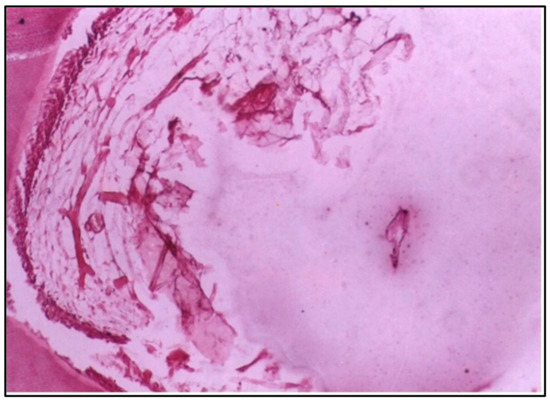

At 6 weeks, the pulp tissue exhibited more pronounced destructive changes. The central region of the pulp and the area adjacent to the cavity showed degeneration, indicating that the pulp tissue was unable to recover and was undergoing significant damage (Figure 2).

At 6 weeks, more severe changes were evident, with destructive alterations in the central pulp region and the areas adjacent to the cavity. These findings could indicate a failure to adapt to the material or prolonged inflammatory response, potentially due to the prolonged exposure to residual monomers or other components of the resin [18]. In addition, the destructive changes in the pulp adjacent to the cavity at 6 weeks may be attributed to the proximity of the restorative material to the pulp. It is conceivable to suggest that the cavities used in the present study, although of a depth of 0.5 mm, are considered deep because of the small thickness of the enamel and dentine of puppies’ primary teeth, which is about 0.7 mm.

Figure 2. LS of the pulp (Group I, 6 weeks) showing obvious destructive changes in the central region and the side of the pulp adjacent to the cavity (H & E Stain, ×100).